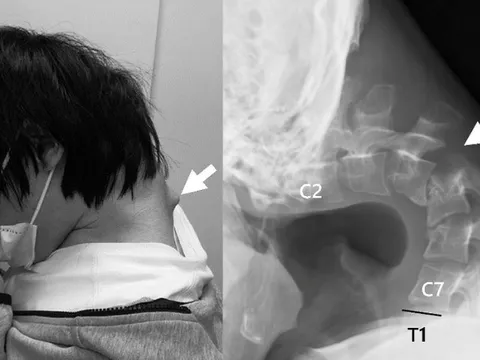

Thanh niên 25 tuổi cúi đầu xem điện thoại đột ngột đau cổ dữ dội, không thể ngẩng đầu, suýt liệt cổ: Cảnh báo giới trẻ

Sau một thời gian, anh bắt đầu xuất hiện các triệu chứng nghiêm trọng: đau cổ dữ dội, không thể ngẩng đầu và khó nuốt, gây sụt cân nhanh chóng.